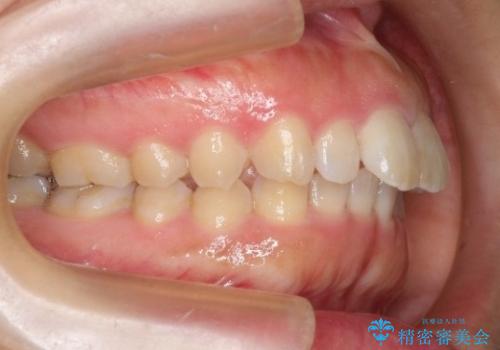

【出っ歯が気になる】インビザライン症例

- 前歯の歯並びの改善を希望され来院された患者様です。

初診時の歯並びの状態としては、上の前歯が下に対して前に飛び出た上顎前突という状態で、前歯は大きく前に飛び出した状態により患者様も口の閉じづらさを感じているとのことでした。また上顎に軽度の叢生(ガタガタ)がありました。

抜歯は行わず上顎の奥のスペースを利用して歯をスライドする方法の他に歯列弓の拡大やディスキング(歯と歯の間の隙間を作る処置)を行い叢生を改善しました。

奥歯を後ろに送る工程では上下でゴムかけをしていただきました。

矯正装置としてはマウスピースを使用しています。

見た目、嚙み合わせ及び、治療期間や施術内容に大変ご満足いただきました。